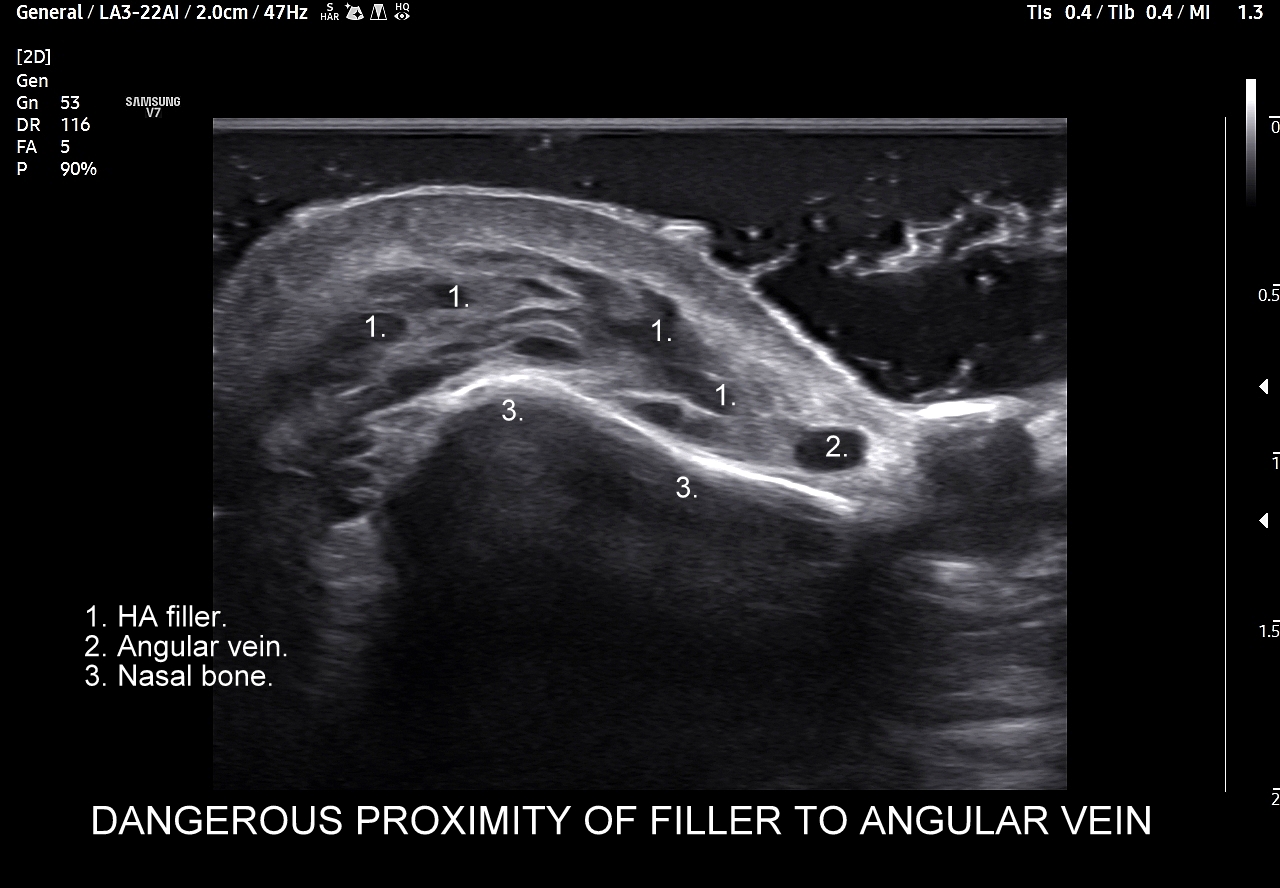

Należy również podkreślić, iż ze względu na gęste upakowanie naczyń, bezpośrednią bliskość anastomoz i często obecność szerokiej, acz niewidocznej żyły kątowej szczególnie niebezpiecznym w aspekcie deponowania wypełniaczy czy wystąpienia lokalnych stanów zapalnych jest obszar u nasady nosa, przy wewnętrznych kącikach oczu i na gładzinie (łac. glabella). Na załączonych do artykułu skanach zobaczyć można czym jest trójkąt śmierci na twarzy i na tej podstawie uzmysłowić sobie, dlaczego tak właśnie się nazywa. Proszę zwrócić uwagę na przykład ekstremalnej bliskości nieodpowiedzialnie zdeponowanego u podstawy nosa wypełniacza, tu kwasu hialuronowego, w stosunku do struktur naczyniowych.